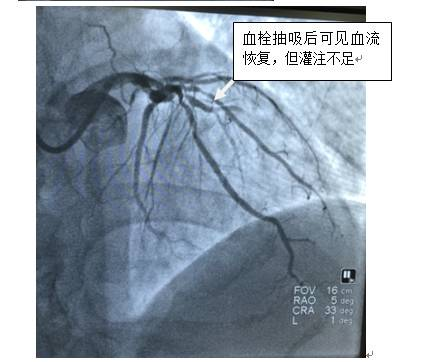

心内科王立娟医师接到电话后马上意识到情况严重性,于是立即通知PCI(经皮冠状动脉介入治疗)小组组织抢救。病情就是命令!当时是夜里11点,包括中山一院外派专家胡洵医师、练飞鸿医师、张素如护士在内的PCI小组人员在接到通知后20分钟内已经赶到DSA治疗室,迅速完善术前准备工作,马上为患者进行急诊手术。术中证实患者左前降支已经完全堵塞,经过血管内血栓抽吸治疗,患者冠脉血运总算得以恢复。没想到,危险还没度过,患者此时出现了反复室性心动过速,情况紧急!抢救团队立即对患者进行静脉药物抢救治疗,并再次造影,证实患者冠脉病变为弥漫性狭窄。PCI小组成员沉着冷静,从容应对,经过球囊扩张,顺利为患者植入冠脉支架。两个小时过去了,手术室里紧张的气氛渐渐散去,经过努力,患者堵塞的血管得以疏通,胸痛症状缓解,脱离生命危险。